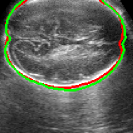

As mentioned in Sec. 3.2, it is crucial for our brain extraction network to work consistently regardless of the orientation of the brain within the US volume. This can be qualitatively observed in Fig. 3, which shows the outline of the brain-extraction prediction and the corresponding ground-truth, in red and green respectively, for six different 3D US volumes. These volumes have been selected to demonstrate the amount of variation between each scan, with the position of the fetus inside the mother as well as the position of the brain in respect to the scan varying drastically from case to case.

As shown in Fig. 3 , the network’s prediction is remarkably close to the ground-truth, regardless of the position of the brain in the volume. It also manages to accurately predict the location of the brain when this is partially obscured either by the cropping or the shape of the ultrasound beam.